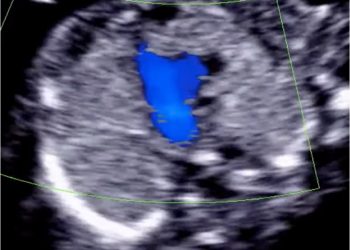

Cari soci, questo mese un nuovo video "How to do", sulla valutazione ecografica dell'endometrio e della cavità uterina secondo il...